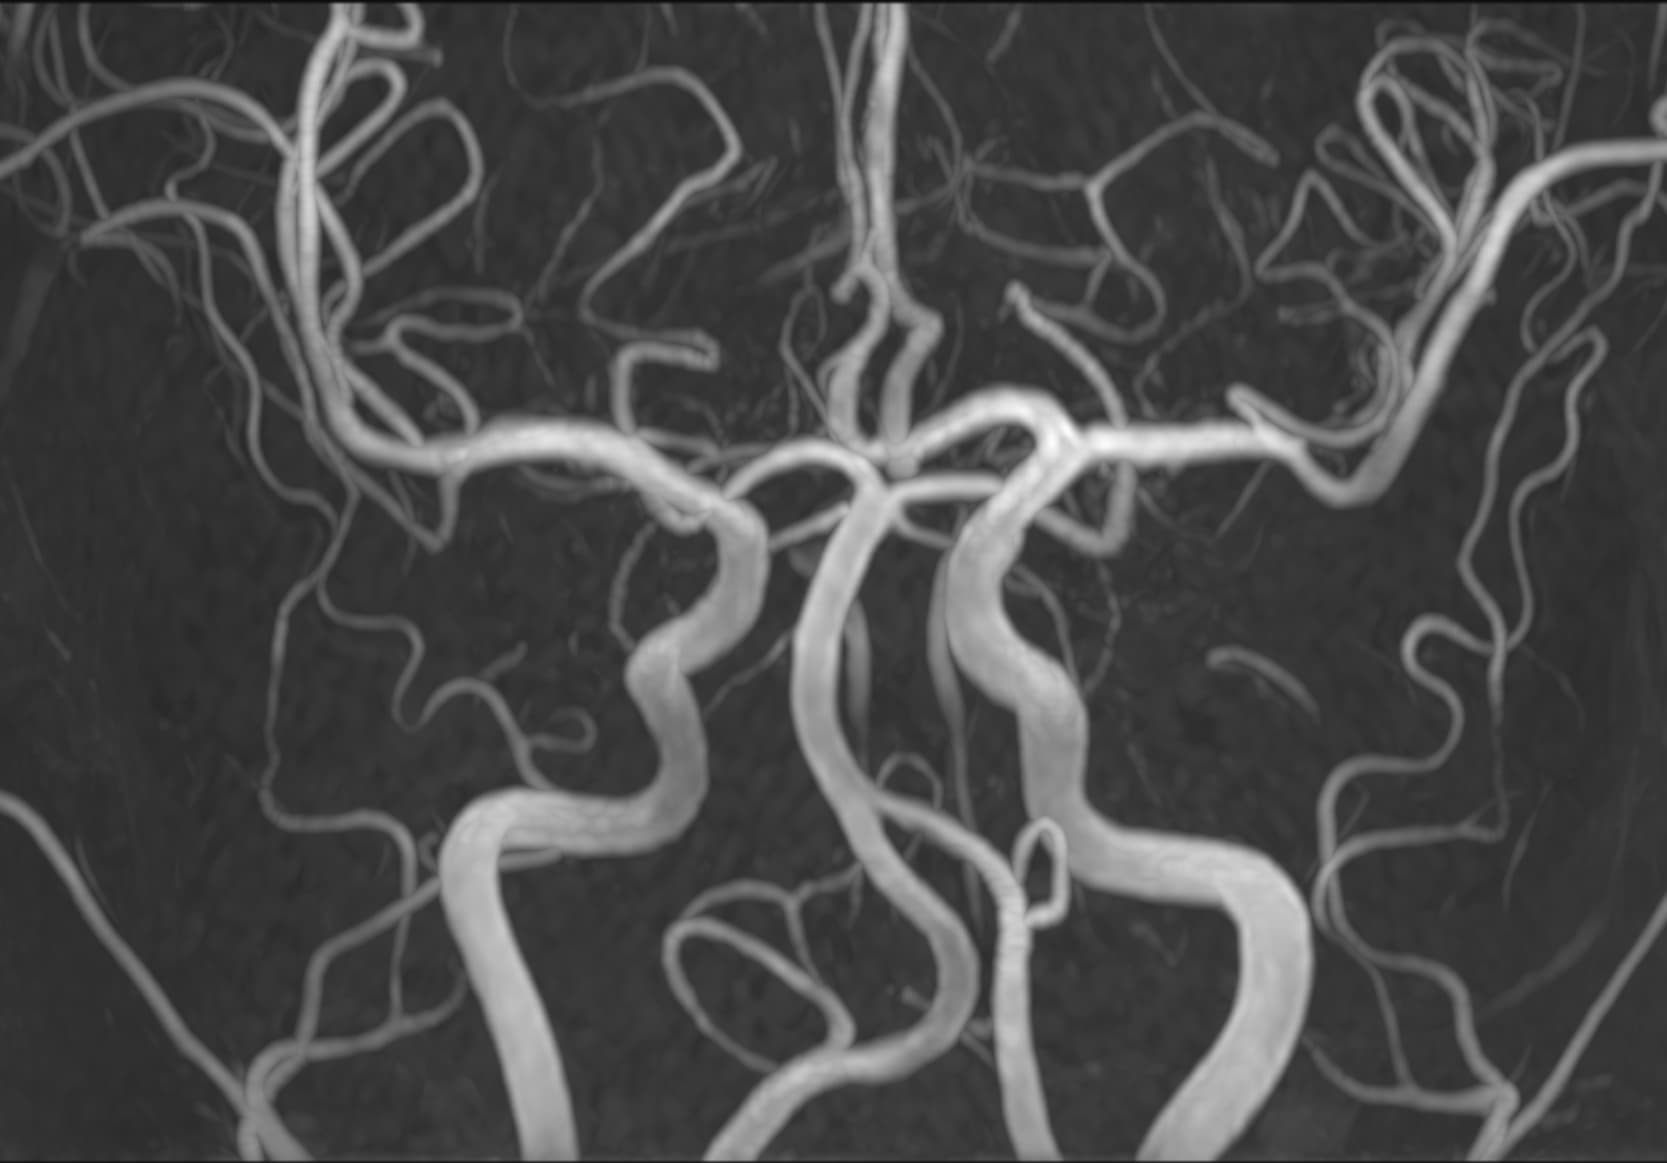

Δείτε πραγματικά παραδείγματα του SwiftMR™ σε διάφορα συστήματα MRI και ανατομικές περιοχές

Scan time 03:14

Scan time 02:07